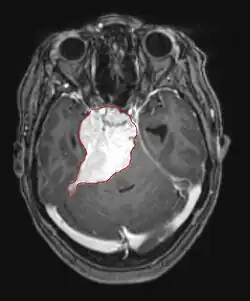

As metástases cerebrais são as neoplasias intracranianas mais comuns em adultos, sendo dez vezes mais comuns que os tumores cerebrais primários. Eles pisam em 20 até 40 por cento dos adultos com câncer e estão associados principalmente ao câncer de pulmão e mama e melanoma . Essas lesões resultam da disseminação de células cancerígenas pela corrente sanguínea e ocorrem mais comumente na junção da substância cinzenta e branca, onde a seção transversal dos vasos sanguíneos se altera, aprisionando embolias de células tumorais . 80 por cento das lesões ocorrem nos hemisférios cerebrais, 15 por cento no cerebelo e 5 por cento no tronco cerebral. Cerca de 80 por cento dos pacientes têm história de câncer sistêmico e 70 por cento têm múltiplas metástases cerebrais.

Avanços significativos foram feitos recentemente no diagnóstico e tratamento dessas lesões, resultando em melhora da sobrevida e controle dos sintomas. O início dos sinais e sintomas é semelhante ao de outras lesões maciças no cérebro. O método diagnóstico de escolha é a ressonância magnética com meio de contraste.

A literatura mostra resultados equivalentes para cirurgia e radiocirurgia. Este último parece ser mais conveniente, eficaz e seguro para lesões pequenas ou em regiões inacessíveis à cirurgia. A radiocirurgia é uma alternativa sensata para pacientes que não podem ser operados por razões médicas. No entanto, a cirurgia é claramente o método ideal para obter tecidos para diagnóstico e remover as lesões que causam efeito de massa. Portanto, a radiocirurgia e a cirurgia devem ser melhor consideradas como dois métodos complementares, mas diferentes a serem aplicados, dependendo da situação diferente do paciente. Por quase 50 por cento dos pacientes com uma ou duas metástases cerebrais não são candidatos à remoção cirúrgica devido à inacessibilidade das lesões, extensão da doença sistêmica ou outros fatores. Esses e outros pacientes com metástases múltiplas geralmente recebem radioterapia panencefálica como padrão de tratamento. Na verdade, chegar até quase 50 por cento deles com esta terapia uma melhora nos sintomas neurológicos e 50 até 70 por cento uma reação perceptível. A quimioterapia raramente é usada principalmente para metástases cerebrais.

Para a maioria dos pacientes com metástases cerebrais, a sobrevida média é de apenas quatro a seis meses após a radioterapia panencefálica. No entanto, pacientes com menos de 60 anos com lesões discretas e doença sistêmica controlada podem alcançar maior sobrevida porque podem tolerar uma abordagem de tratamento mais agressiva.